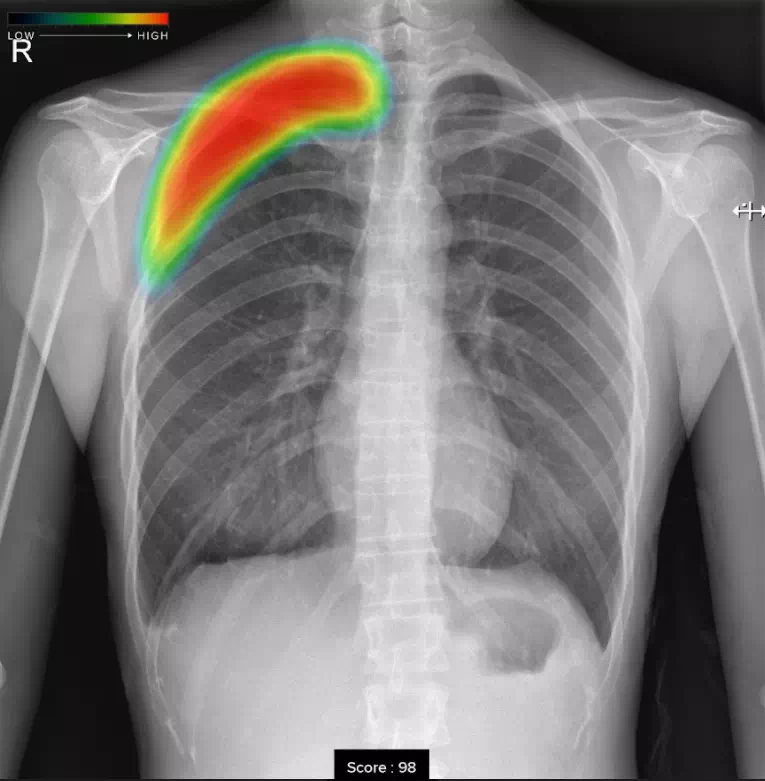

気胸

ヒートマップ表示機能

AIが異常の可能性がある領域を自動解析し、確信度に応じた表示を行います。確信度のスコアは0~100の範囲で設定され、画像上では色分けされたヒートマップとして示されます。

スコア表示機能

0~100の範囲で確信度スコアの最大値が数値として表示されます。